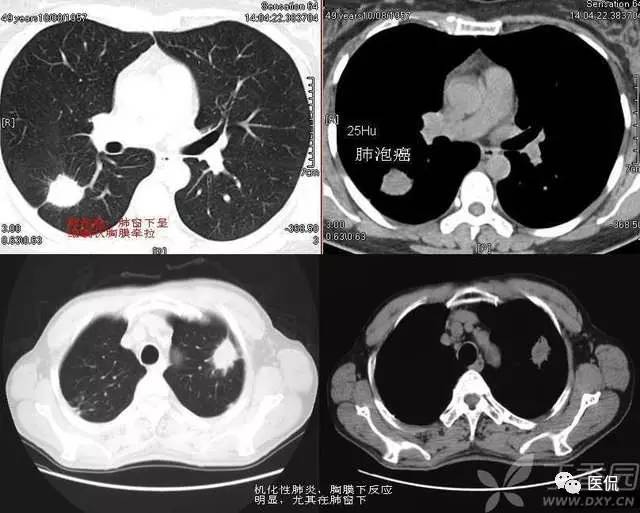

胸膜下弧线(SCLC)

肺胸膜下弧线影像(SCLS)的病理基础

国外学者对此征象的CT与病理对照研究指出,SCLS是细支气管周围纤维性增厚及肺纤维化引起的肺泡变扁和肺不张。构成SCLS的肺不张为肺脏皮质与髓质交界处的盘状肺不张,肺不张的发生与肺间质纤维化后肺脏的顺应性减低有关。指出肺脏蜂窝状改变的边缘融合也可形成SCLS,SCLS位于蜂窝之间,这在HRCT图像上可清楚地显示。临床发现,SCLS发生在慢性肺炎之后,少数发生在慢性支气管炎合并肺间质纤维化患者吸气不足状态,深吸气时大部分消失,也有发生在阻塞性肺不张后,这些表明SCLS为肺脏局部通气不良发生的盘状肺不张。胸膜广泛钙化,SCLS与胸膜钙化的范围一致,肺内也有轻度的肺间质纤维化改变,胸膜钙化可能使胸膜下肺组织的顺应性下降,从而对SCLS的形成有促进作用。胸膜增厚与胸膜结节也可能引起类似的结果。

SCLS的HRCT形态特点

SCLS与生理性的肺下垂部线性影像不同,生理性胸膜下线位于肺脏的最低部,在仰卧位时位于下叶后部,而转变为俯卧位时下叶后部的线性影像消失,生理性胸膜下线多距胸膜下5mm以内,可合并局限性肺脏密度增高。而SCLS虽然在肺脏后部多见,但多超过一个肺段的范围,并可位于肺脏非下垂的部位。体位变换时其形态无变化,也不会消失。多数SCLS表面光滑、呈连续状,少数为不规则及不连续状。煤工尘肺的SCLS可有结节状影,或厚度较大。

SCLS的诊断意义

SCLS可见于多种肺间质纤维化的疾病,如慢性支气管炎合并肺间质纤维化,煤工尘肺,特发性肺间质纤维化,胶原病引起的肺间质纤维化,及结节病引起的肺改变等。慢性支气管炎,特发性肺间质纤维化,煤工尘肺及胶原病引起的肺脏改变等均可出现,占90.3%。以往一些作者曾认为SCLS在石棉肺多见,或认为此征象是石棉肺病人的特有表现。但临床研究的结果表明,SCLS是肺间质纤维化的一种常见征象,见于多种疾病。此外,SCLS还见于炎症、肺瘀血和吸气不足状态。对于肺间质纤维化的病例,SCLS为肺间质纤维化的早期改变。

SCLS周围无肺间质纤维化征象者占25.71%,仅有小叶内间质增厚及小叶间隔增厚者占28.57%,发生较多蜂窝改变的仅占20%。SCLS的长度与肺间质纤维化的严重程度有关,有人对随访的肺间质纤维化逐渐加重的患者,发现SCLS也由短线型发展为长线型。即使SCLS可发生在有蜂窝的部位,但蜂窝改变多较轻微,而在蜂窝改变较密集之处未能见到SCLS。有研究指出,SCLS开始发生在肺间质纤维化轻微的部位,5年后该部位发生严重蜂窝改变,SCLS则不能显示。这表明SCLS的发生、延长与肺间质纤维化加重有关,但出现严重蜂窝后SCLS则不能显示。

总之,SCLS可以变小或消失,表明SCLS有些为可逆的改变。不同的疾病SCLS在形态上多无显著的差异。煤工尘肺SCLS可有细小结节,此结节与肺内结节的形态相似,代表了煤工尘肺的形态特点。但对大多数疾病而言,SCLS缺乏鉴别诊断价值。